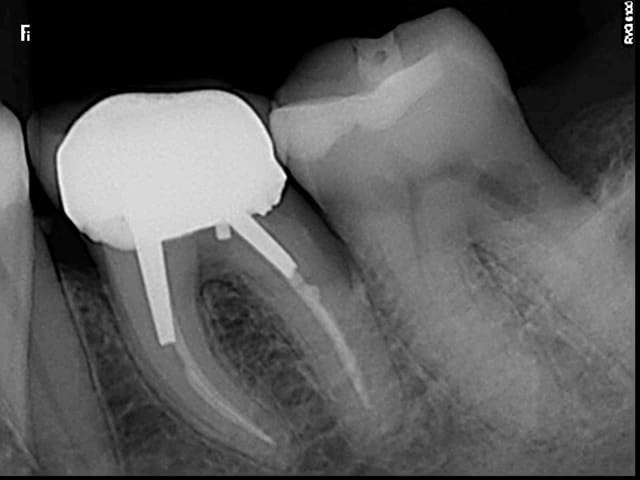

Bonjour, la patiente présente les signes d'une pulpite débutante sur 37 et à la radio j'ai trouvé çà : une lacune (érosion interne?) de forme atypique...j'ai pris plusieurs clichés avec angulations différentes.

Quelqu'un sait il ce que c'est ? Le diagnostic ? J'envisage le TC, des précautions particulières ?

Si ce n'est pas une lésion externe (noter la perte osseuse au niveau de la racine distale), ce serait plus une résorption interne qu'une érosion interne, non?

Je confirme, aucune lésion externe vestibulaire, distale ou linguale. Résorption interne ou lacune à angles nets, quelles sont les causes ? Traitement spécifique ou endo traditionnelle ? (je suis la patiente en paro depuis plusieurs années).

slt à toi. il semble s'agir d'une résorption interne.

POur confirmer ton diagnostic tu dois avoir 2 rétro alvéolaires dont une décentrée de 30°. Tu peux également faire un conbeam bien que pas indispensable.

Le traitement est simple il faut faire le traitement canalaire car l'évolution de résorption interne est plus rapide qu'une externe. obturation gutta chaude.

nicklebenou : oui c pour etre sure que j'ai pris 2 autres clichés un distalé et un mésialé.

Donc résorption interne, les dentinoclastes s'énervent on ne sait pas vraiment pourquoi. Je ne pense pas à une cause occlusale. Patiente totalement dentée, pas de signes, sa spécificité est plus sa pathologie parodontale. Ce peut il etre la cause ?

Bref, je vais faire le TC, avec temporisation hydroxyde de Ca pendant 1mois, puis gutta chaude.

Entre la première et la deuxième radio, tu as clairement un décalage de la lésion.

De plus les contours du canal distal sont très nets sur toutes les radios

On devine une résorption osseuse sur cette racine distale

Donc pour moi tout indique que c'est externe

Finalement oui je révise mon diag et pense à une externe aussi.

Même si je n'en suis pas certain à 100%. On voit bien le canal distal défini en effet derrière la lésion de résorption. Après je pense que les clichés sont décalés ne le sont pas assez pour se faire une meilleure idée mais il semble que la lésion soit décalée entre les clichés 1 et 2 par rapport au canal donc externe aussi.

Je ferai un CBCT pour vérifier le point d'entrée et voir pour la suite.